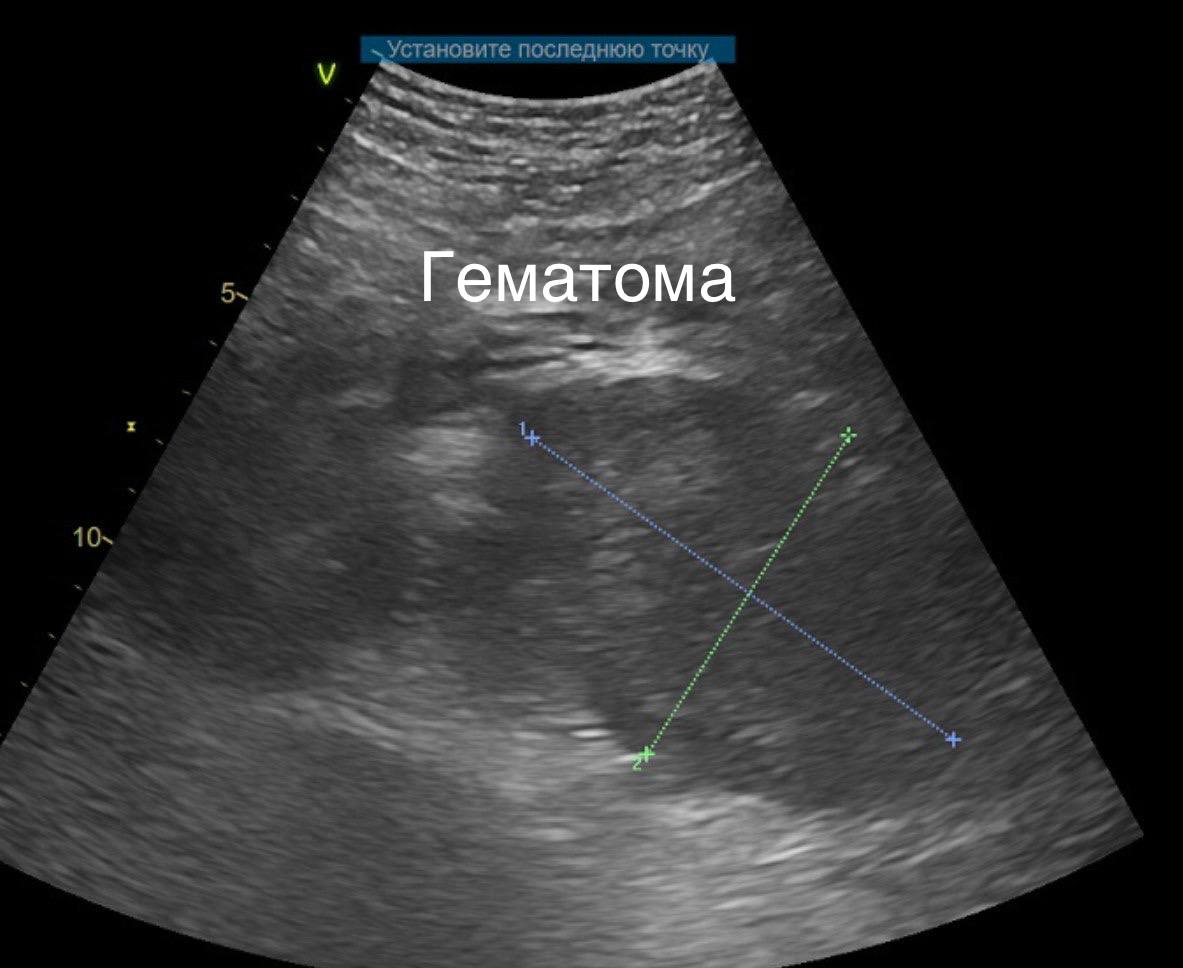

В центр экстренной медицины НИИ скорой помощи им. И.И. Джанелидзе поступил пациент с кататравмой (травмой при падении с высоты). Мужчина, упав на поясничную область, получил серьёзное повреждение – разрыв левой почки IV степени с продолжающимся кровотечением и образованием забрюшинной паранефральной гематомы.

Раньше в подобных случаях для оценки повреждения часто требовалось время, а решение об операции принималось в условиях дефицита информации. Сегодня стандартом стала экспресс-визуализация. Пациенту в приёмном отделении экстренно выполнили компьютерную томографию (СКТ) с контрастным усилением, которая включила исследование грудной клетки, брюшной полости и таза. Это позволило за считанные минуты: